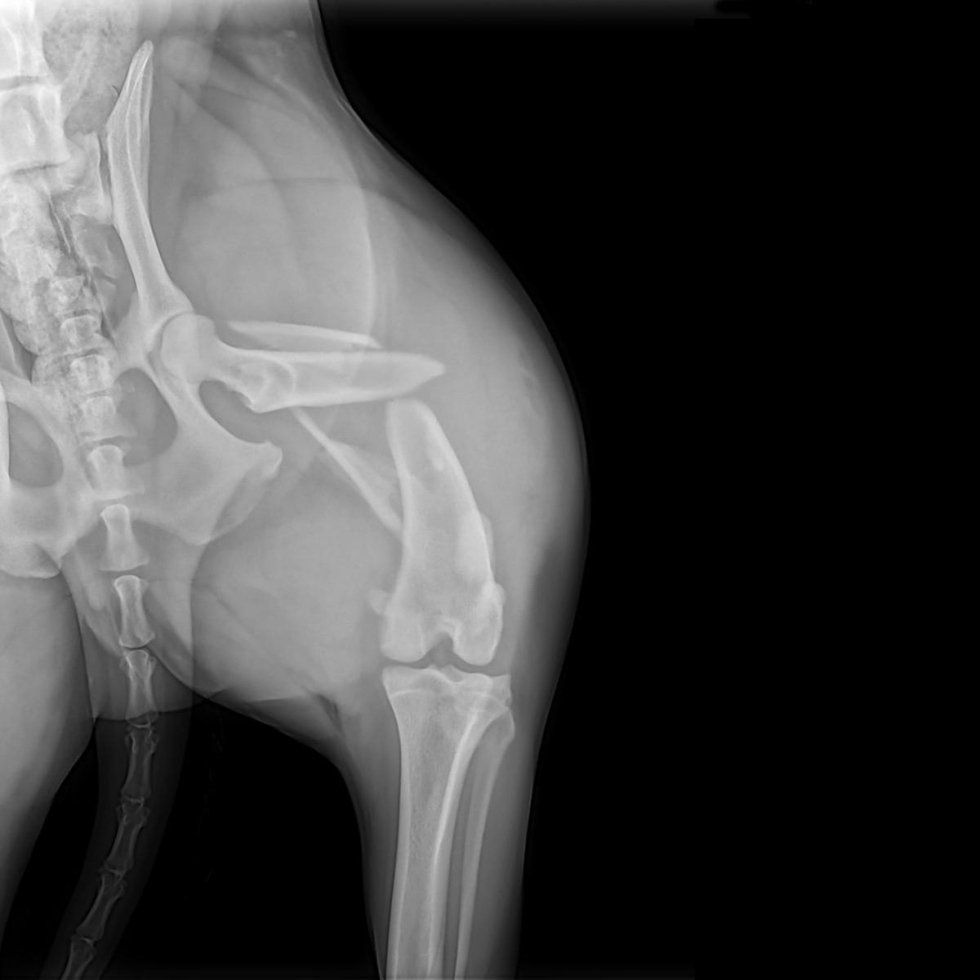

Ortopedia è una specialità veterinaria incentrata sulla diagnosi e la riparazione delle lesioni che coinvolgono ossa, articolazioni e legament.

Particolare attenzione si dedica ad un attento studio radiografico preventivo, effettuato alle razze dei cani che hanno un'alta percentuale di malattia ortopedica ereditata(displasia dell'anca e del gomito,lussazione della rottula) in un periodo compreso tra 4-5 mesi d’età.

Sono diverse le patologie ortopediche che interessano la articolazione del gomito, articolazione della spalla e articolazione dell’anca del cane. Problemi di lussazione della rotula in cani di piccola taglia e non, procedure di carattere chirurgico – traumatologico dell’ossa e dei tessuti moli periarticolari.

Osteotomia del collo e della testa del femore è una procedura meno costosa di una protesi d'anca o una chirurgia pelvica, se la procedura è quella corretta, ci si può aspettare una buona ripresa in un cane piccolo. Razze di dimensioni piu grandi avrebbero alcuni segni di zoppia e di dolore della articolazione trattata.